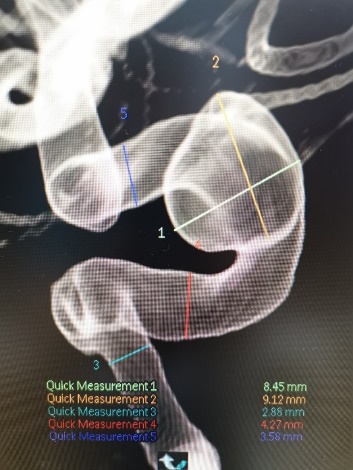

入院后行全脑血管造影证实右侧颈内动脉眼段动脉瘤。瘤颈宽约4.91mm,瘤体最大径约8.21mm,载瘤动脉远近端血管直径分别为3.07mm、3.52mm。

术前造影: